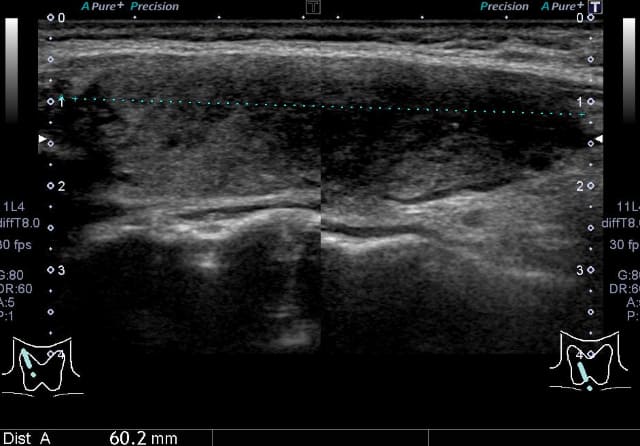

甲状腺超音波(エコー)検査では、甲状腺は基本的には全体的に大きくなり、内部は粗くみえることが多いです。臨床診断は、甲状腺の全体的な腫大に加えて、TgAbまたはTPOAb陽性で行います。甲状腺機能が正常であれば治療の必要はありません。機能が低下している場合には飲み薬(チラーヂンS®、レボチロキシン®)によって甲状腺ホルモンの補充を行います。服用は一日一回です。(吸収の安定性からは空腹時の服用がよく、また金属系製剤と同時服用は避ける必要があります)